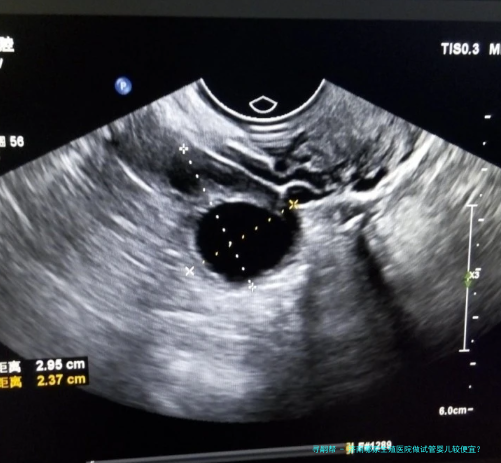

诊断费:对于试管婴儿技术,起首需要进行诊断,以认定病患是不是适合进行试管婴儿技术,病人的生殖系统肿瘤、妊娠合并症等情况,所以诊断费是必不可少量的。一般来说诊断费用约为一千元左右。检查费:检查费包括试管婴儿助孕技术评介、腹腔镜检查、辅助生殖技术检查等,一般情况下,检查费用约为2000元左右。药物费:在试管婴儿技术过程当中,需要适当的药物支持,多见的药物费用有激素费、人工受精费、着床技术费等,一般情况下,药物费用约为3000元左右。医疗费:医疗费主要包括试管婴儿技术手术费用及精子搜集费用等,正常情况下,医疗费用约为5000元左右。住院费:如果需要实行住院手术,依旧要支付住院费用,正常情况下,住院费用约为3000元左右。孕检费:试管婴儿技术完成后,须要定期进行孕检,以确定胎儿是否是生长正常,通常情况下,孕检费用约为2000元左右。

在济南生殖医院进行试管婴儿技术普通须要花费3万元左右。但实际费用还需要根据患者的实际情况而定,因而针对您的情况,建议您前往济南生殖医院进行具体咨询,以确定更准确的费用。